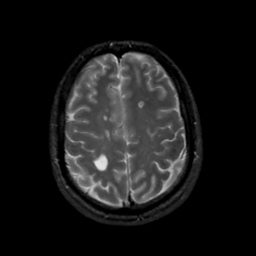

MR Study #13, May 19, 1991 -- Slice #38